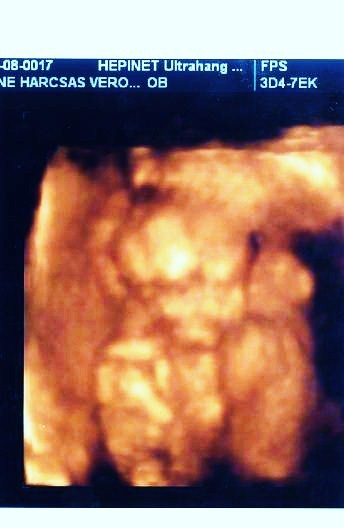

Neked is köszi a választ! Remélem nálunk is elmúlik majd az ellenőrzésre...vagy 25. hétre, mikor megint 4d-re megyek.

A lepényt ultrahangon tudják megnézni, hogy hol tapad. Én a 4D genesist ajánlom nagyon, és a Baross utcába semmiképp ne menj! Az előbbi helyen 10.500ft a vizsgálat, amiben benne van a 30perces vizsgálat, amit egy az egyben dvd-re vesznek, maga a dvd, és egy szép nyomtatott szines kép. Plussz 1500ft-ért kérhetsz egy cd-t is, amire sok képet tesznek, én 53-at kaptam, és a media marktban mind elő is hívattuk.